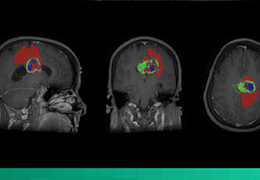

ART-Plan™ Artificial Intelligence Contouring